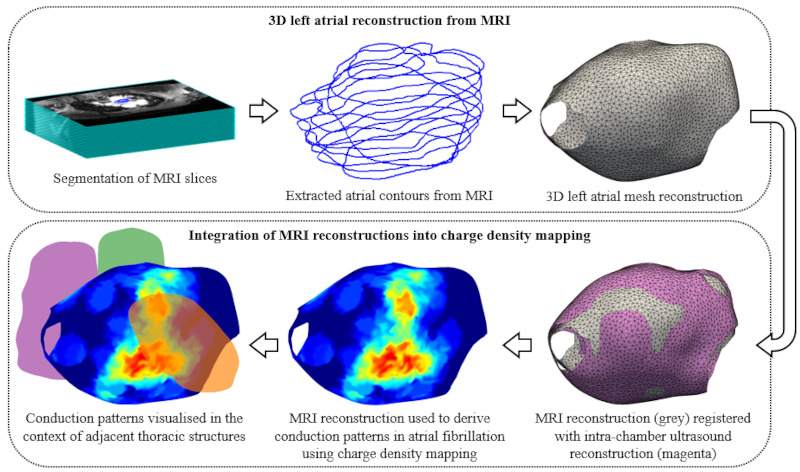

Researchers at the University of Oxford and Oxford University Hospitals have developed a new way to combine magnetic resonance imaging (MRI) with an advanced electrical mapping technique that could improve treatment for patients with persistent atrial fibrillation (AF), the most common abnormal heart rhythm condition. By merging detailed MRI with charge density mapping, which shows how electrical signals move through the heart during AF, doctors may be better able to identify exactly where to target treatment.

MRI is crucial because it provides high-resolution images of the heart's structure. Dr Banerjee’s MultiMeDIA lab specialises in multimodal medical data integration, and was therefore perfectly poised to develop a new computer tool that creates detailed 3D reconstructions of the heart's left atria from MRI scans. These reconstructions were then integrated with charge density mapping, which shows the patterns of electrical conduction during AF. This combination provides doctors with both structural information from MRI and detailed electrical patterns from charge density mapping - essentially creating a more complete picture of what may be causing AF in a patient.

When testing their new approach, the researchers found that problematic electrical patterns were more likely to occur in areas where the heart was close to other structures in the chest, like the aorta and spine. This suggests that pressure from these neighbouring structures might contribute to AF in some patients.